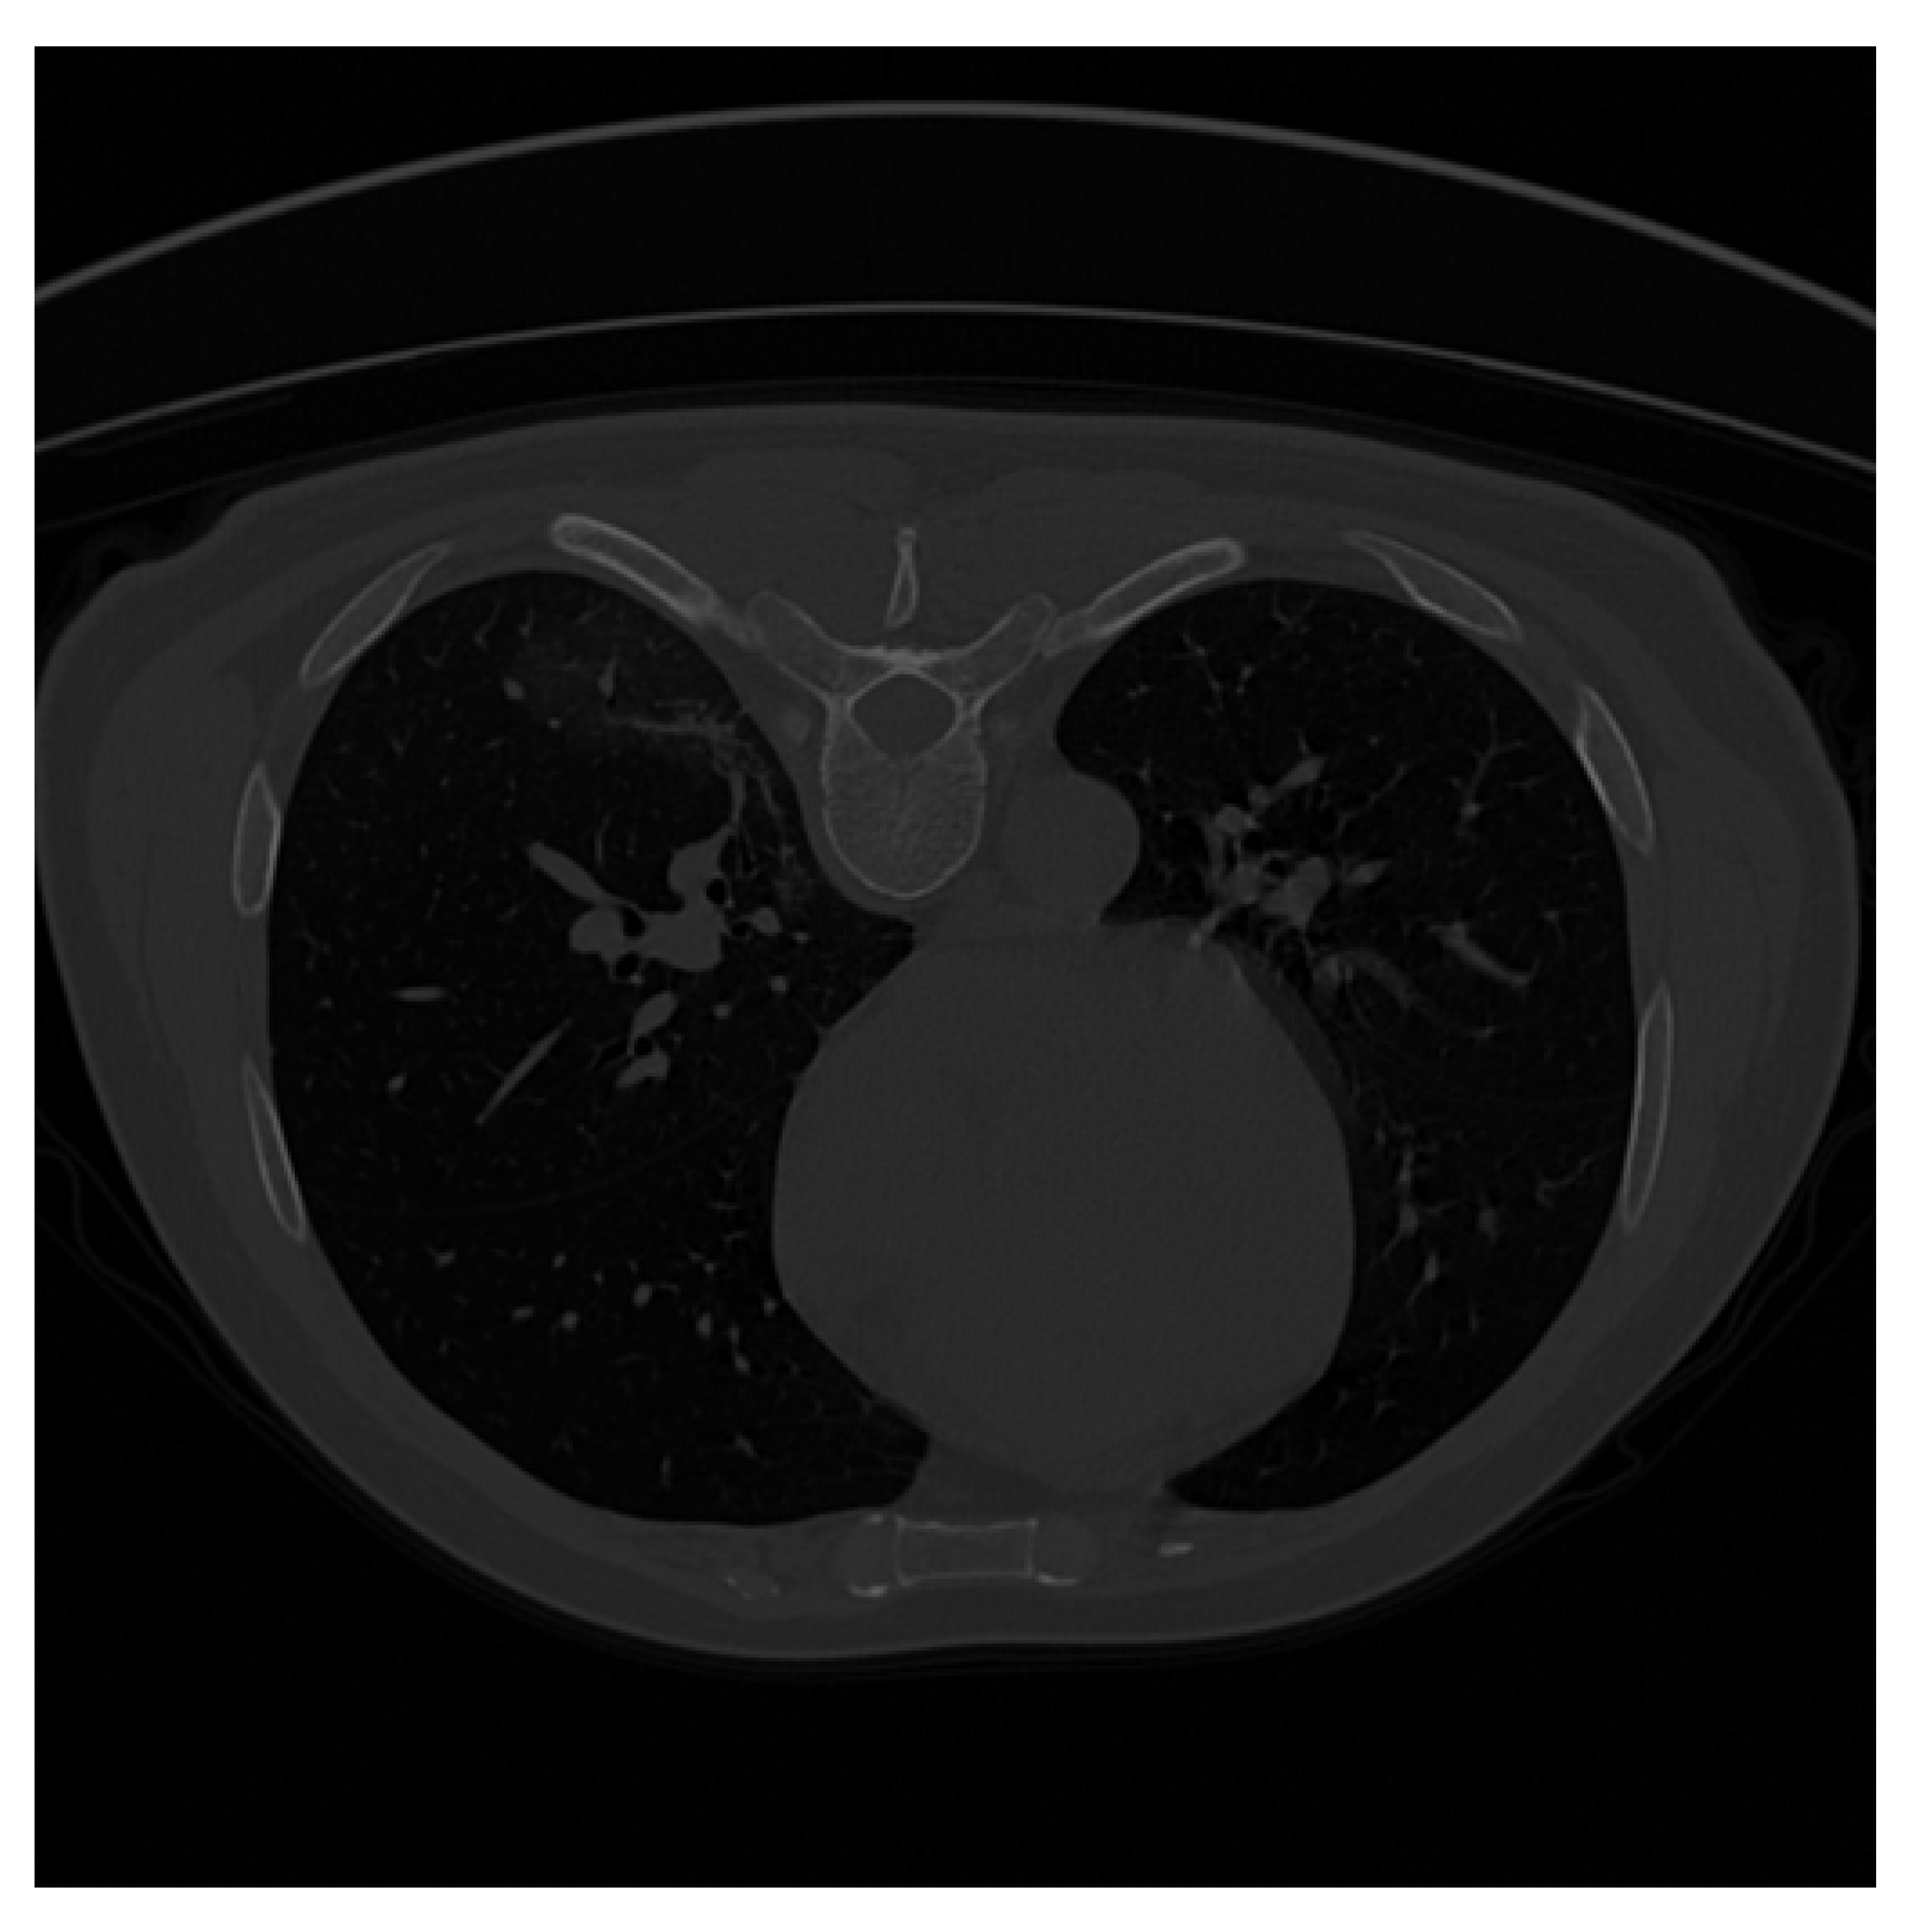

| Original CT Scan | Lung Mask | Infection Mask | Lung and Infection Masks |

|---|---|---|---|

![]() | ![]() | ![]() | ![]() |